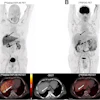

Participants ranged in age from 46 to 93, 648 (64%) were women, and 367 (39%) were carriers of the apolipoprotein E (APOE) ε4 susceptibility gene. All patients underwent beta-amyloid PET scans either with F-18 flortaucipir or F-18 MK-6240 PET radiotracer, with findings based on standardized uptake value ratios (SUVRs) of the tracers in specific brain areas of interest.

According to the results, higher temporal tau SUVR was associated with significantly faster cognitive decline in women than men, based on their performances over an average of 8.6 years on standard cognitive tests.

Specifically, women had higher tau than men across four regions: the parahippocampal gyrus (β = −0.1, p = 0.02), the fusiform gyrus (β = −0.08, p < 0.01), the inferior temporal gyrus (β = −0.09, p = 0.02), and the middle temporal gyrus (β = −0.06, p = 0.01), which are regions associated with early and later stage tau spread, the researchers reported.